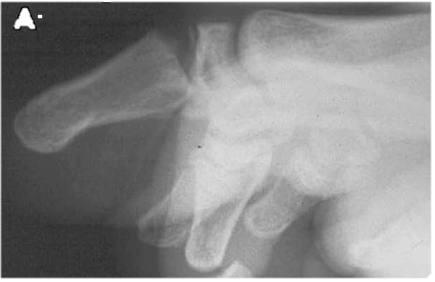

Altrettanto particolare è il quadro della frattura di Pinckney, ovvero di distacco epifisario tipo Salter-Harris II di F2 di I dito, con associata avulsione ungueale. Analoga alla frattura di Seymour nella mano, a tutti gli effetti, è da considerarsi come una frattura esposta e come tale deve essere trattata (figura 8)

Figura 8